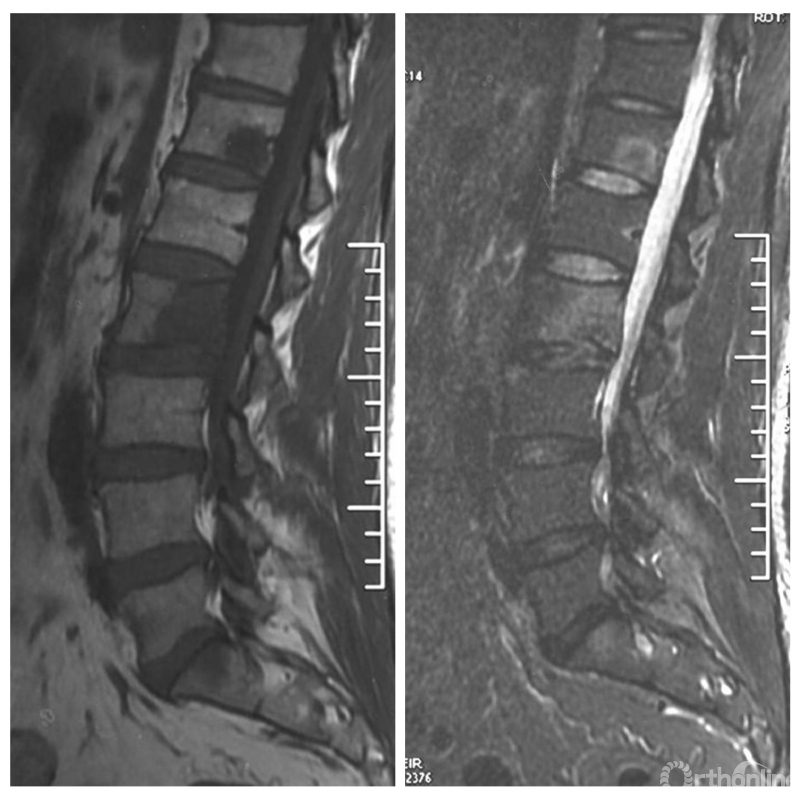

入院影像学资料

经脊柱转移瘤专业评估,ESCC分级为Grade2,对放疗不敏感;SINS评分8分,中度不稳。Karnofsky功能状态评分90%,预计生存时间6个月。NOMS流程建议分离手术和SRS。

常规分离手术可进行360°脊髓减压,充分固定恢复脊柱稳定;但由于其暴露范围广泛,创伤较大,并不适宜患者当前治疗。

为进一步减少创伤,获得更好的综合疗效。骨采用经皮内固定的微创杂交技术,暨经皮内固定结合小切口分离手术,手术失血900ml,术后7天出院。